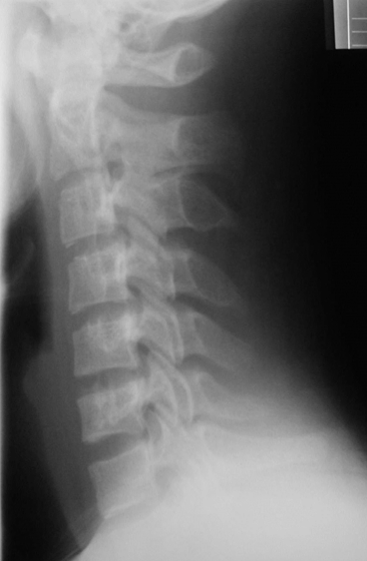

Which cervical line has the most pertinent abnormality?

A

Anterior body line displays slight anterolisthesis

unilateral facet dislocation